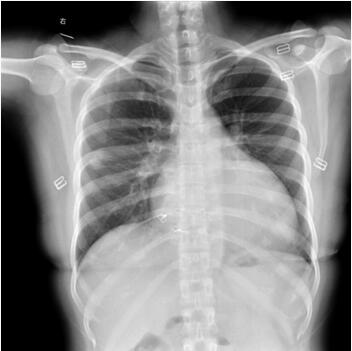

15天前患者开始出现咳嗽,在当地医院 “抗感染”等治疗后感胃胀、食欲减退,伴全身水肿、乏力,并诉活动后气喘、心悸。一天前 (约晚11时),患者突发右侧腰痛,当地医院就诊查血常规正常、尿潜血阴性,未治疗,转至我院急诊,查尿常规正常;尿淀粉酶2098U/L;血凝分析:PT 19.4秒,D二聚体2.99μg/ml;肌钙蛋白T<0.1ng/ml;生化检查:谷氨酸转氨酶185.9U/L,天冬氨酸转氨酶104.4U/L,尿素9.14mmol/L,钙1.92mmol/L,钠132.5mmol/L;X线胸片:右下肺少许炎症可能、两侧少量胸腔积液可能、心影增大(图77-1);心电图:窦性心律,Ⅰ、Ⅱ导联ST段压低;超声心动图:心功能不全,左心室、右心室腔内多枚不规则团块状回声。为进一步诊治收入院。

图77-1 X线胸片显示心影增大、右下肺少许炎症、两侧少量胸腔积液